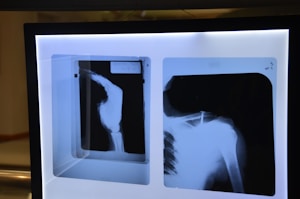

Understanding Greater Trochanteric Pain Syndrome

Greater trochanteric pain syndrome is a common source of pain on the outer side of the hip. Many people…